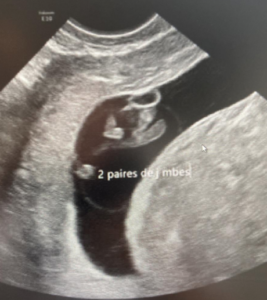

A 33-year-old patient, gravida 1 para 0, presented for a routine examination and dating ultrasound on 06/20/2024. The estimated gestational age was 8 weeks + 6 days. She had no relevant medical history. Her family history was notable for a cousin with trisomy 21. The diagnostic assessment was performed using transabdominal and transvaginal ultrasonography, complemented by three-dimensional (3D) ultrasound. The initial evaluation occurred during a routine first-trimester scan for pregnancy dating at 8+6 weeks of gestation. Ultrasound examination revealed a 23 mm embryo with an enlarged head (Figure 1A). A single gestational sac with two yolk sacs was identified, consistent with a monochorionic–monoamniotic twin pregnancy (Figure 1B).

The ultrasound images demonstrated a single spinal column, two stomachs, and two hearts (Figure 2A). Two fused abdomens were observed, along with subcutaneous edema measuring 2.0 mm and 2.1 mm (Figure 2B). In addition, two pairs of moving legs were identified (Figure 2C). The trophoblast was located anteriorly, and a single corpus luteum was observed in the left ovary. Two follow-up examinations were required at 9 and 10 weeks of gestation to establish the diagnosis. At 9 weeks of gestation, the 3D ultrasound images lacked sufficient clarity for a definitive diagnosis (Figure 3). At 10 weeks of gestation, color Doppler imaging demonstrated two distinct cardiac activities, indicating the presence of two separate circulatory systems (Figure 4A). Three-dimensional imaging further revealed the face of one of the conjoined twins and confirmed the presence of two umbilical cords (Figure 4B).